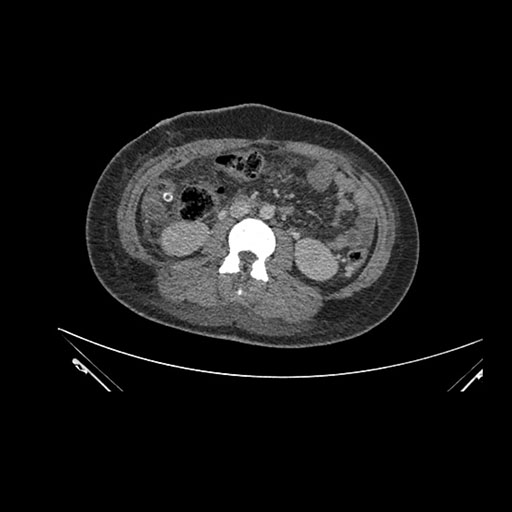

Axial Arterial